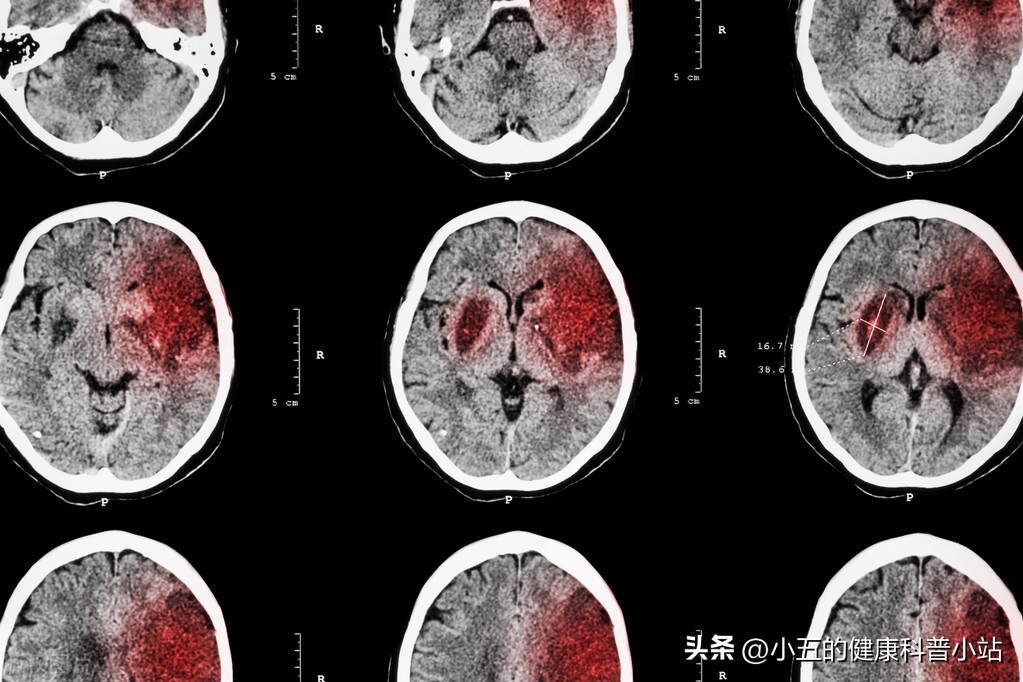

3个多月前王大爷感觉自己左边的肢体有点不对劲,又乏力,又麻木,刚开始他以为没什么事情, 结果当天晚上就出现了左半身的肢体瘫痪,伴有剧烈的头疼、头晕,家属连忙将其送往医院急诊就诊。医生第一时间完善了颅脑CT结果发现王大爷右侧内囊部大面积梗死 ,于是急忙将其收治入院,并且在第一时间进行了血栓再通手术。经过一段时间的治疗, 王大爷左侧肢体的运动功能很快恢复了,复查大脑内的梗死灶面积也明显缩小 ,于是医生为其开具了抗血小板聚集药、降脂稳定斑块药等,并且嘱咐其定期前来医院就诊。

图片来自于网络,侵删